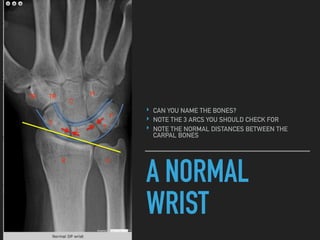

A NORMAL

WRIST

‣ CAN YOU NAME THE BONES?

‣ NOTE THE 3 ARCS YOU SHOULD CHECK FOR

‣ NOTE THE NORMAL DISTANCES BETWEEN THE

CARPAL BONES

A NORMAL WRIST ‣ CANYOU NAME THE BONES? ‣ NOTE THE 3 ARCS YOU SHOULD CHECK FOR ‣ NOTE THE NORMAL DISTANCES BETWEEN THE CARPAL BONES S L T P R U TR TR C H